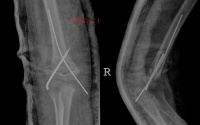

x线特征:受伤后不久可出现局限性肿快。伤后3-4周,在肿快内显示毛状致密象,其临近骨将显示骨膜反应。伤后6-8周,病变边缘部清楚地被致密骨质所包绕,而具有新生骨的外貌。软组织肿块的核心部有时显囊性变且逐渐扩大其内腔,到晚期而显出类似蛋壳状的囊肿。伤后5-6个月肿块收缩,因而肿块与邻近的骨皮质和骨膜反应之间显出x线透亮带。